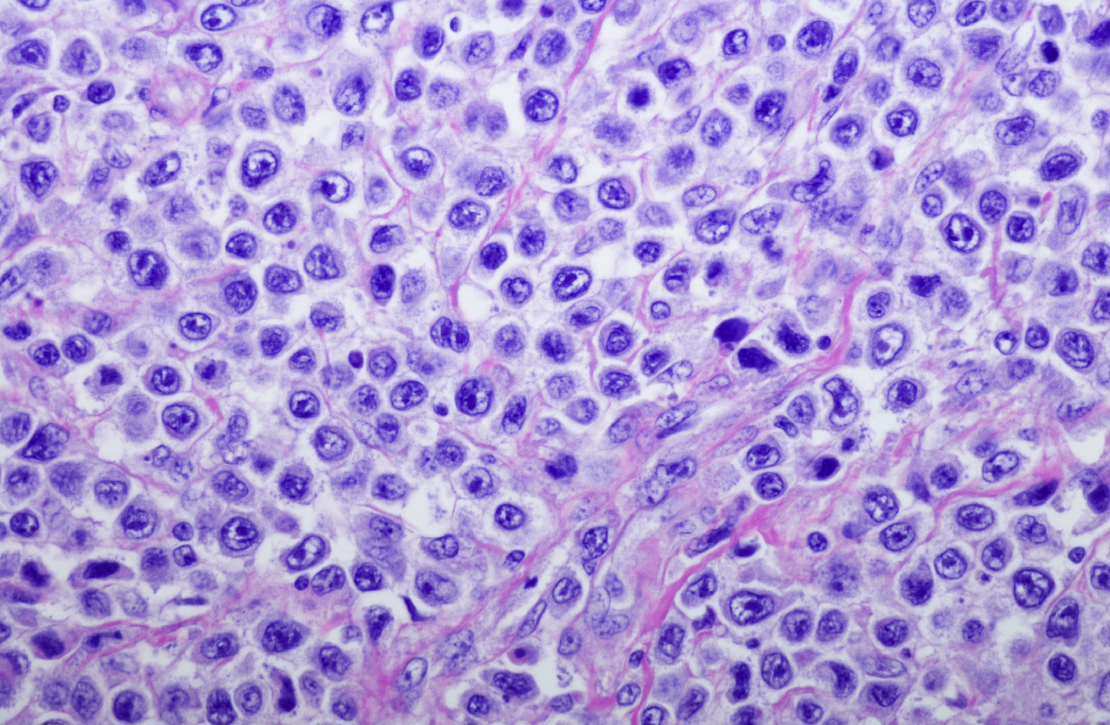

Lymphoma is the most common form of blood cancer, yet public awareness about its symptoms remains low. According to the Lymphoma Coalition, an international network of patient organisations, millions worldwide are living with lymphoma, with over 735,000 new cases diagnosed annually.